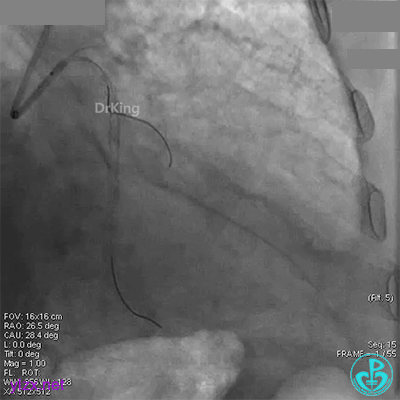

经刺破球囊冠脉内推注硝普钠后血流恢复2级,远端分支血管没有充分显影。

退出分支导丝后造影,血流不足3级。

术后心电图无明显改变。